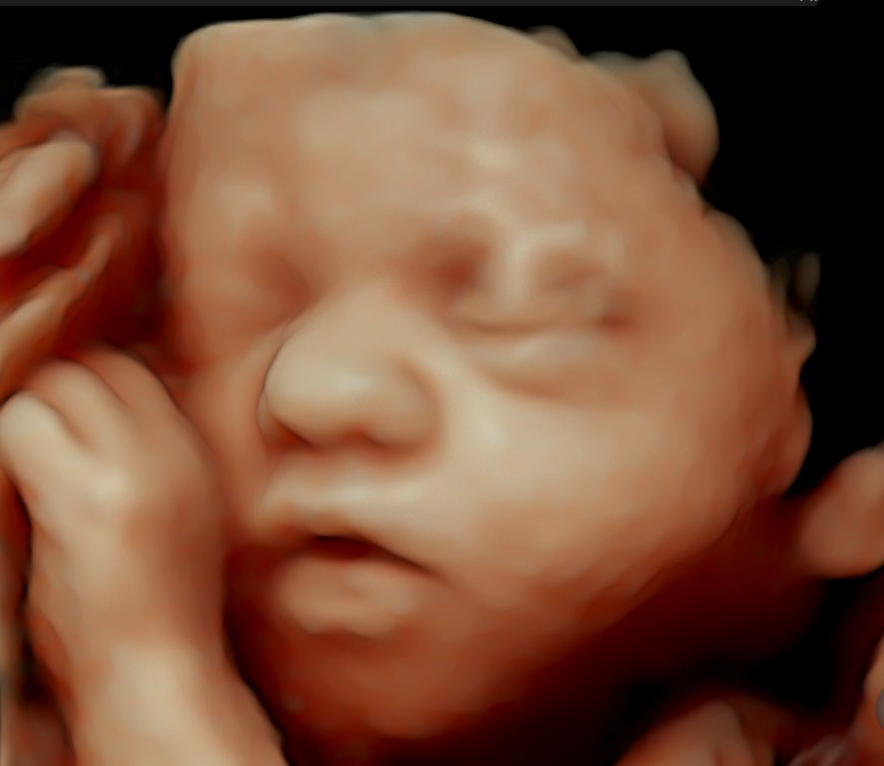

• HDliveTM technologies

El Voluson Signature 18 se basa en un nuevo motor de imágenes: la arquitectura Voluson Unity, que ofrece velocidades de procesamiento y velocidades de fotogramas más rápidas que nuestros sistemas Signature anteriores. Este hardware y software son la base del sistema y sientan las bases para las capacidades actuales y futuras. Experimente ahora un nuevo nivel de profundidad y claridad.

Procesamiento rápido de volumen 3D/4D